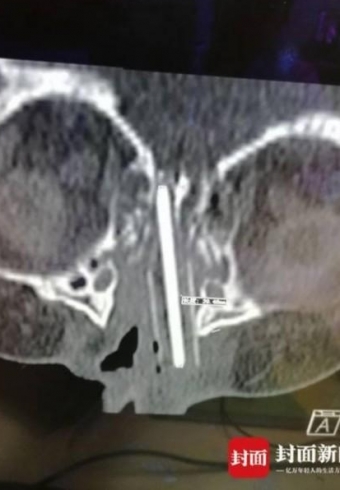

女童玩铅笔不慎戳进鼻腔 医生取出4.5cm残留部分